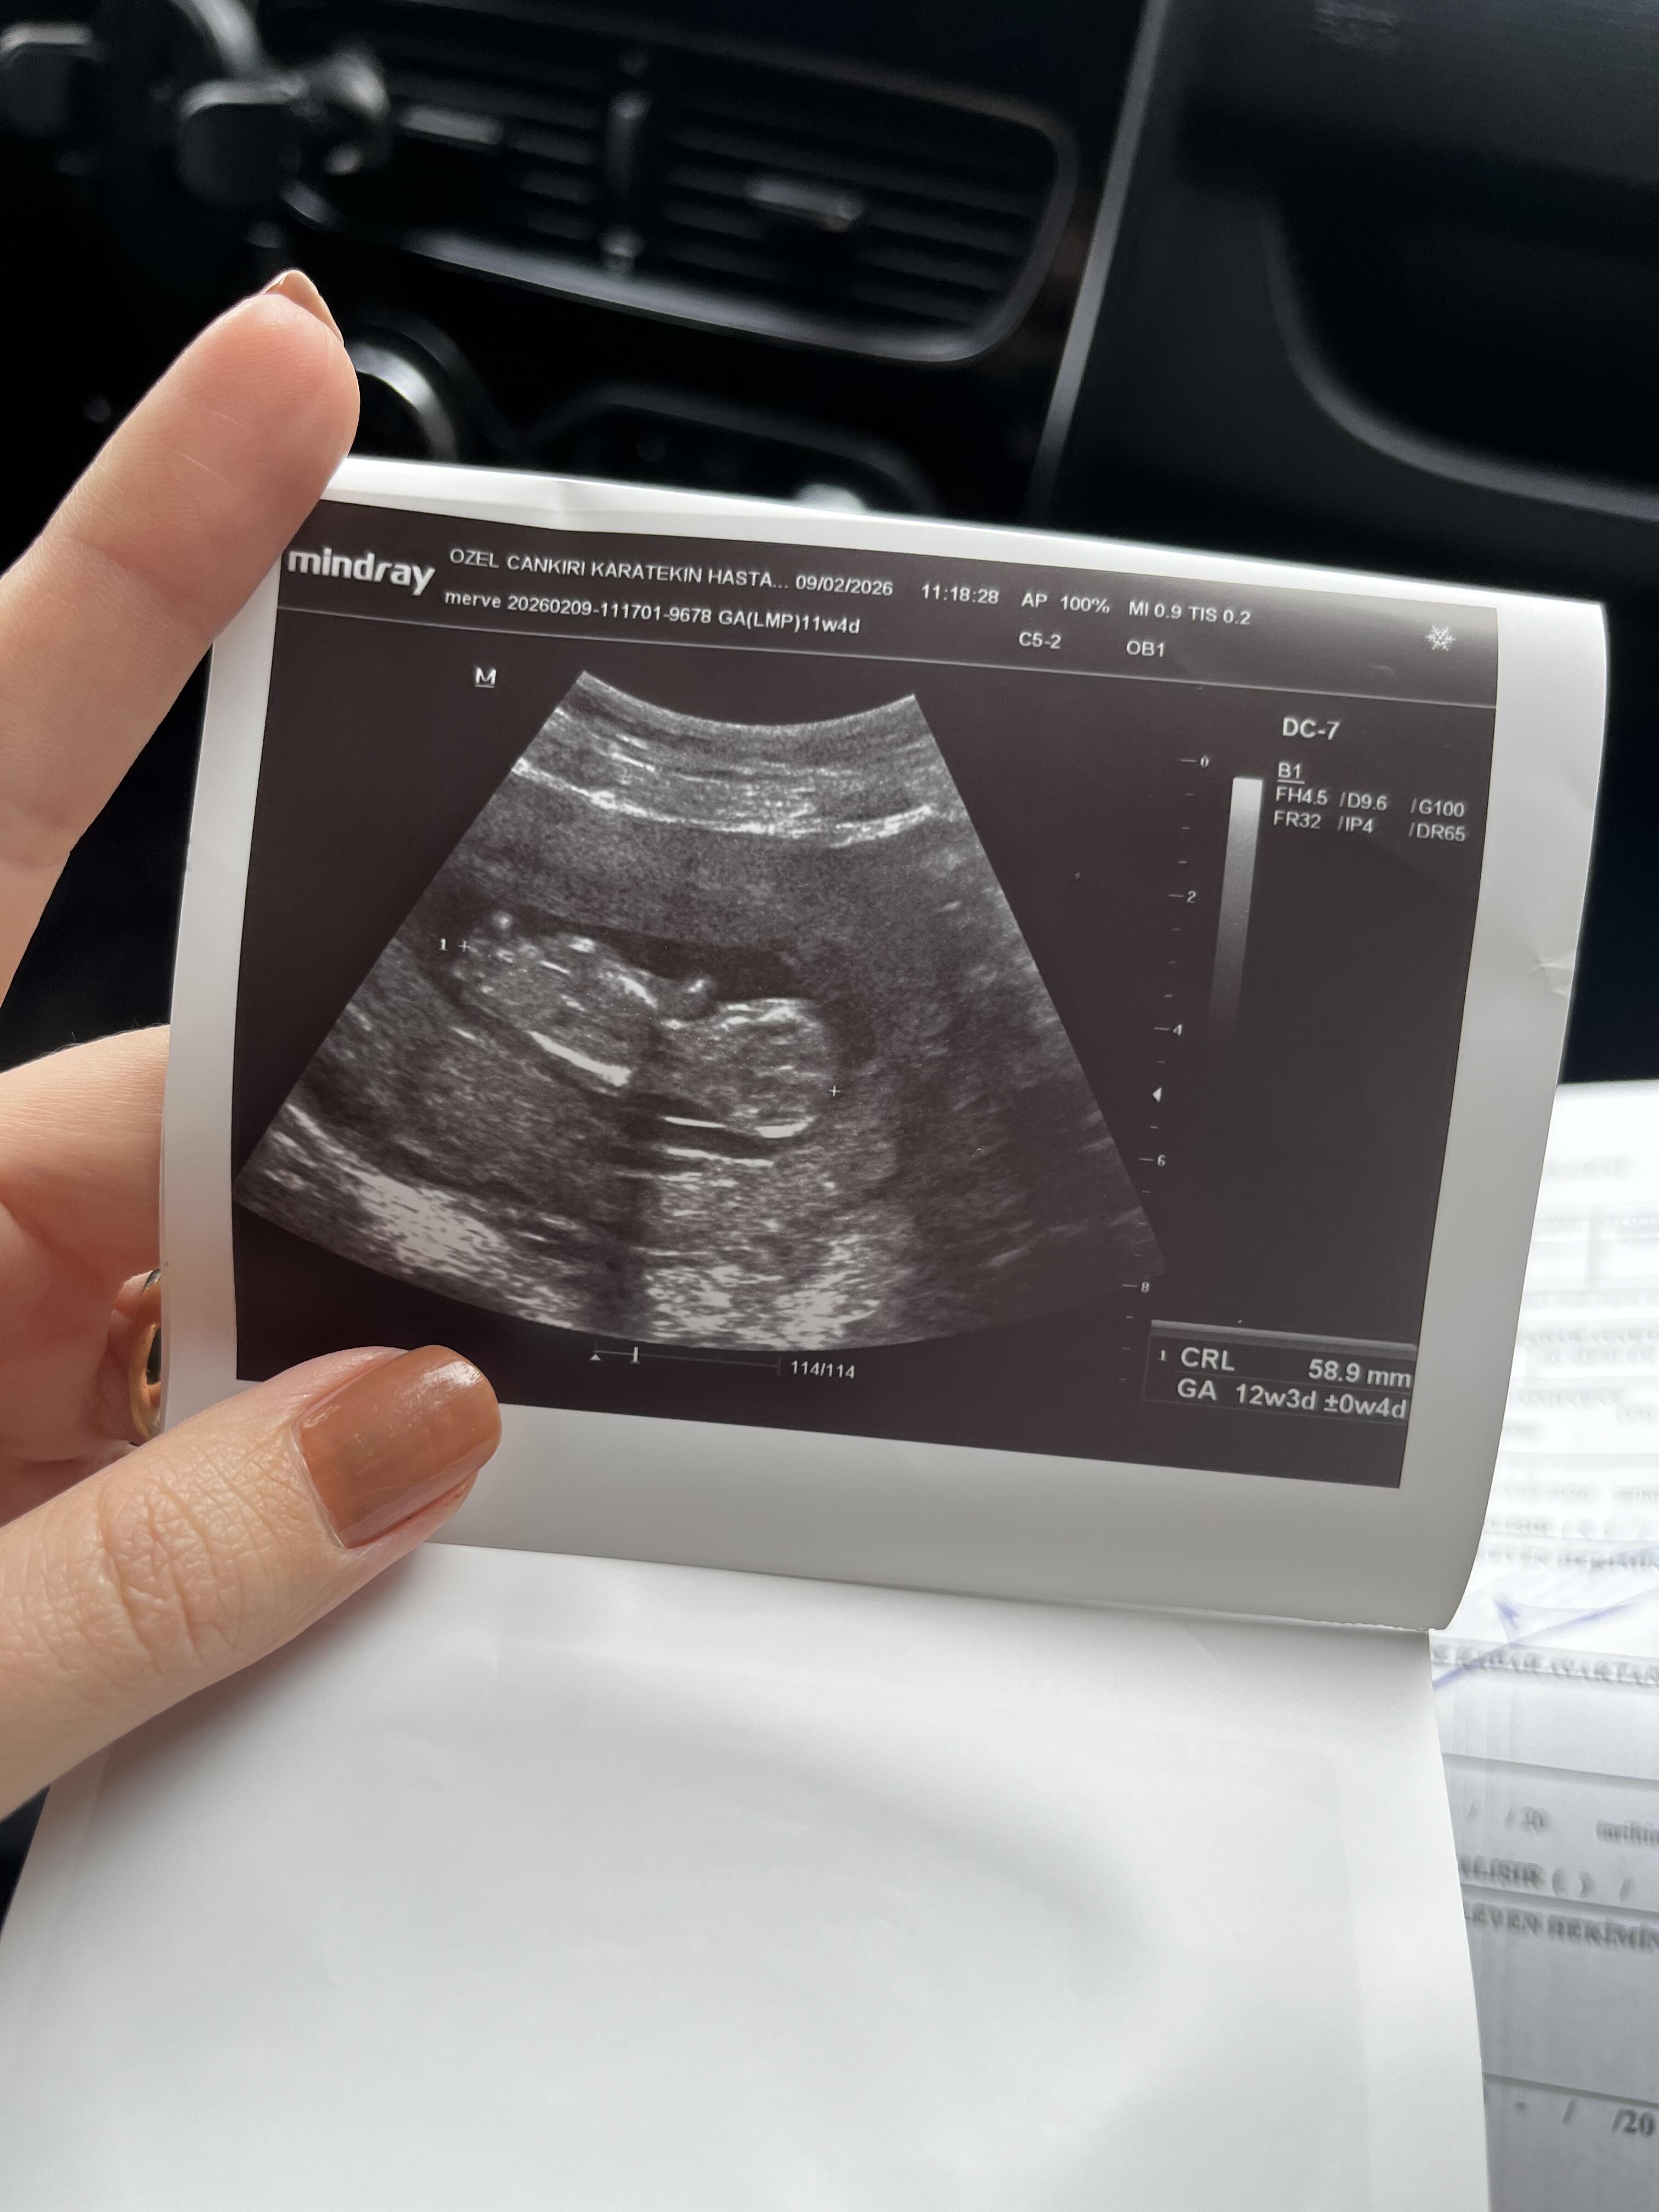

Keseniz şu an oval gibi.İkili test yaptırdınız mı testteki beta HCG değeriniz neydi acaba![]()